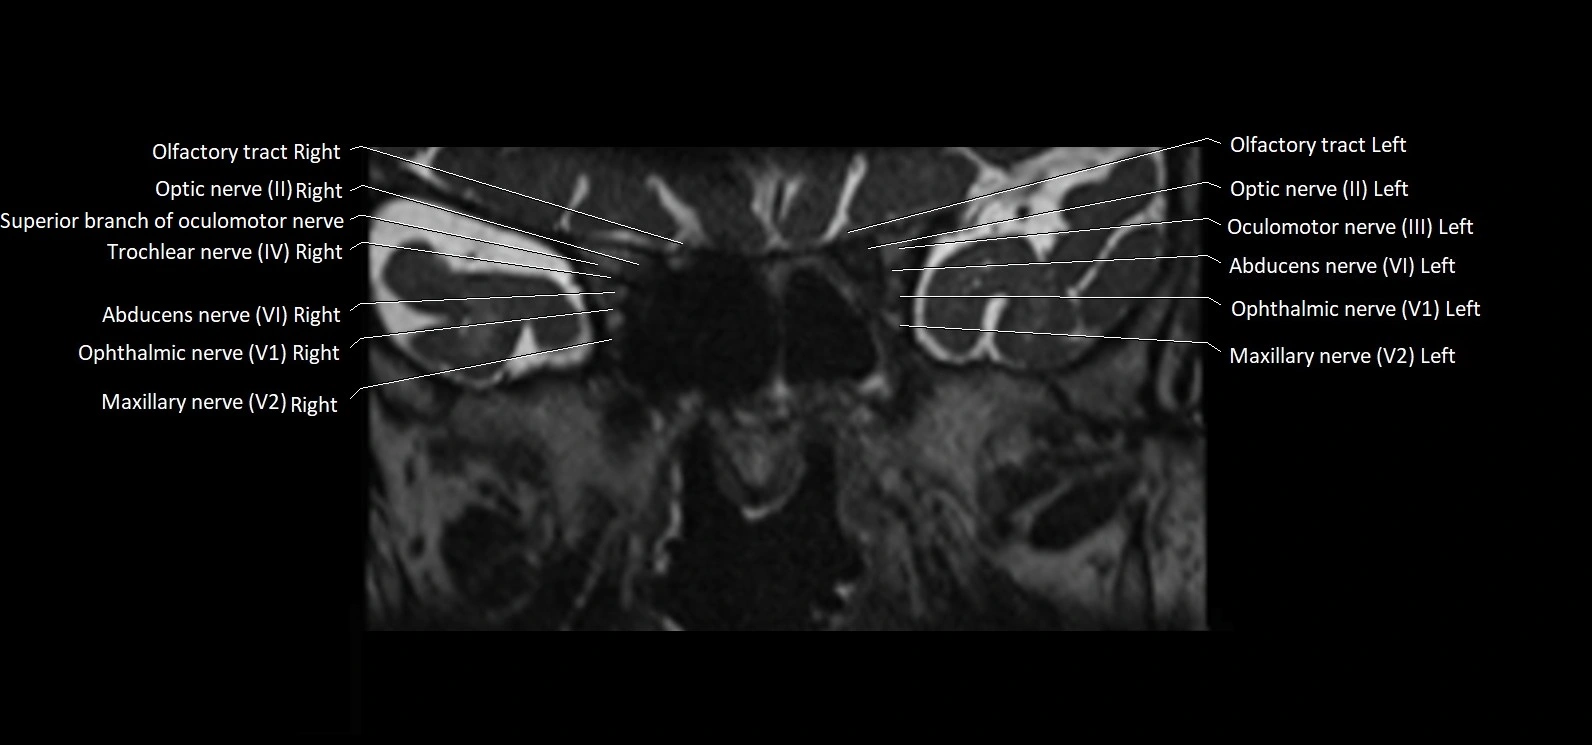

MRI Appearance

• The abducens nerve is a small, thin, linear structure

• Best visualized on high-resolution T2-weighted 3D MRI sequences (e.g., FIESTA or CISS)

• Seen as a hypointense (dark) line running from the brainstem at the pontomedullary junction, traversing the prepontine cistern, and entering Dorello’s canal under the petrosphenoidal ligament, then into the cavernous sinus, and finally the orbit

• May be challenging to visualize in standard MRI due to its small size

• Pathology may be inferred by absence, displacement, or enhancement of the nerve

MRI images

image